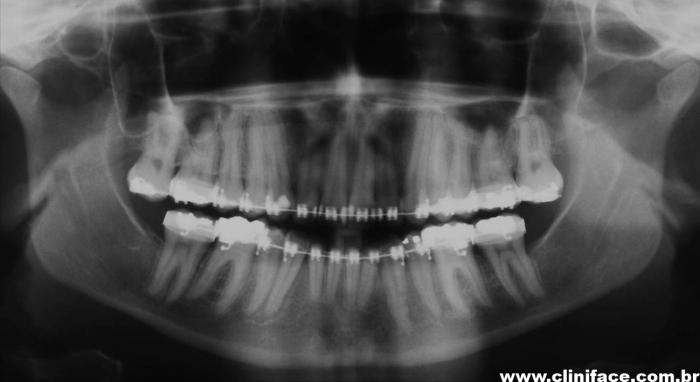

Raio x panorâmico final